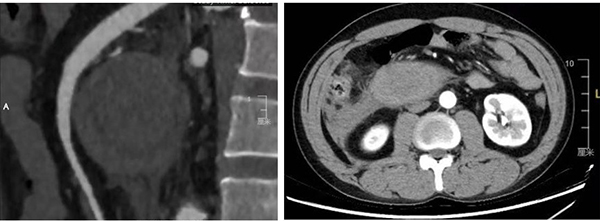

40歲的王先生近期無明顯征兆突發(fā)上腹部劇烈疼痛,還伴隨乏力、惡心等不適癥狀,且在短時間內(nèi)持續(xù)加重,王先生立即前往當(dāng)?shù)厝嗣襻t(yī)院-徐醫(yī)附院醫(yī)聯(lián)體單位就診。腹部CT檢查提示十二指腸占位,周圍存在滲出表現(xiàn);超聲胃鏡檢查進(jìn)一步顯示十二指腸降部有粘膜下隆起,管腔狹窄且伴隨胃潴留。患者病情復(fù)雜,病因不明,經(jīng)積極保守治療,王先生病情仍呈現(xiàn)持續(xù)惡化趨勢,當(dāng)?shù)厝嗣襻t(yī)院普外科緊急聯(lián)系徐醫(yī)附院肝膽胰外科張斌主任,經(jīng)溝通決定將患者轉(zhuǎn)入徐醫(yī)附院進(jìn)一步治療。

時間就是生命,王先生被緊急轉(zhuǎn)診至徐醫(yī)附院肝膽胰外科。入院后,醫(yī)護(hù)人員迅速為其完善CTA腸系膜血管檢查,檢查結(jié)果顯示,患者十二指腸降部占位、遠(yuǎn)端管壁增厚、局部擴(kuò)張積液,腹盆腔還存在明顯滲出、積液,病情十分危急?焖僭u估患者病情,立即聯(lián)系多學(xué)科進(jìn)行會診,邀請麻醉科、影像科、消化內(nèi)科、腫瘤內(nèi)科、介入科等相關(guān)科室專家開展緊急病例討論。此時,王先生的腹痛、嘔吐癥狀持續(xù)加劇,影像學(xué)評估提示其腹盆腔積血較前明顯增加,隨時可能因失血性休克危及生命。雖病因診斷仍存疑問,但患者病情危重、刻不容緩,在普外科學(xué)科帶頭人、肝膽胰外科專家呂凌教授指導(dǎo)下,并與患者家屬充分溝通并獲得同意后,專家團(tuán)隊(duì)當(dāng)機(jī)立斷,決定為患者實(shí)施外科開腹探查手術(shù),盡全力搶救患者生命。